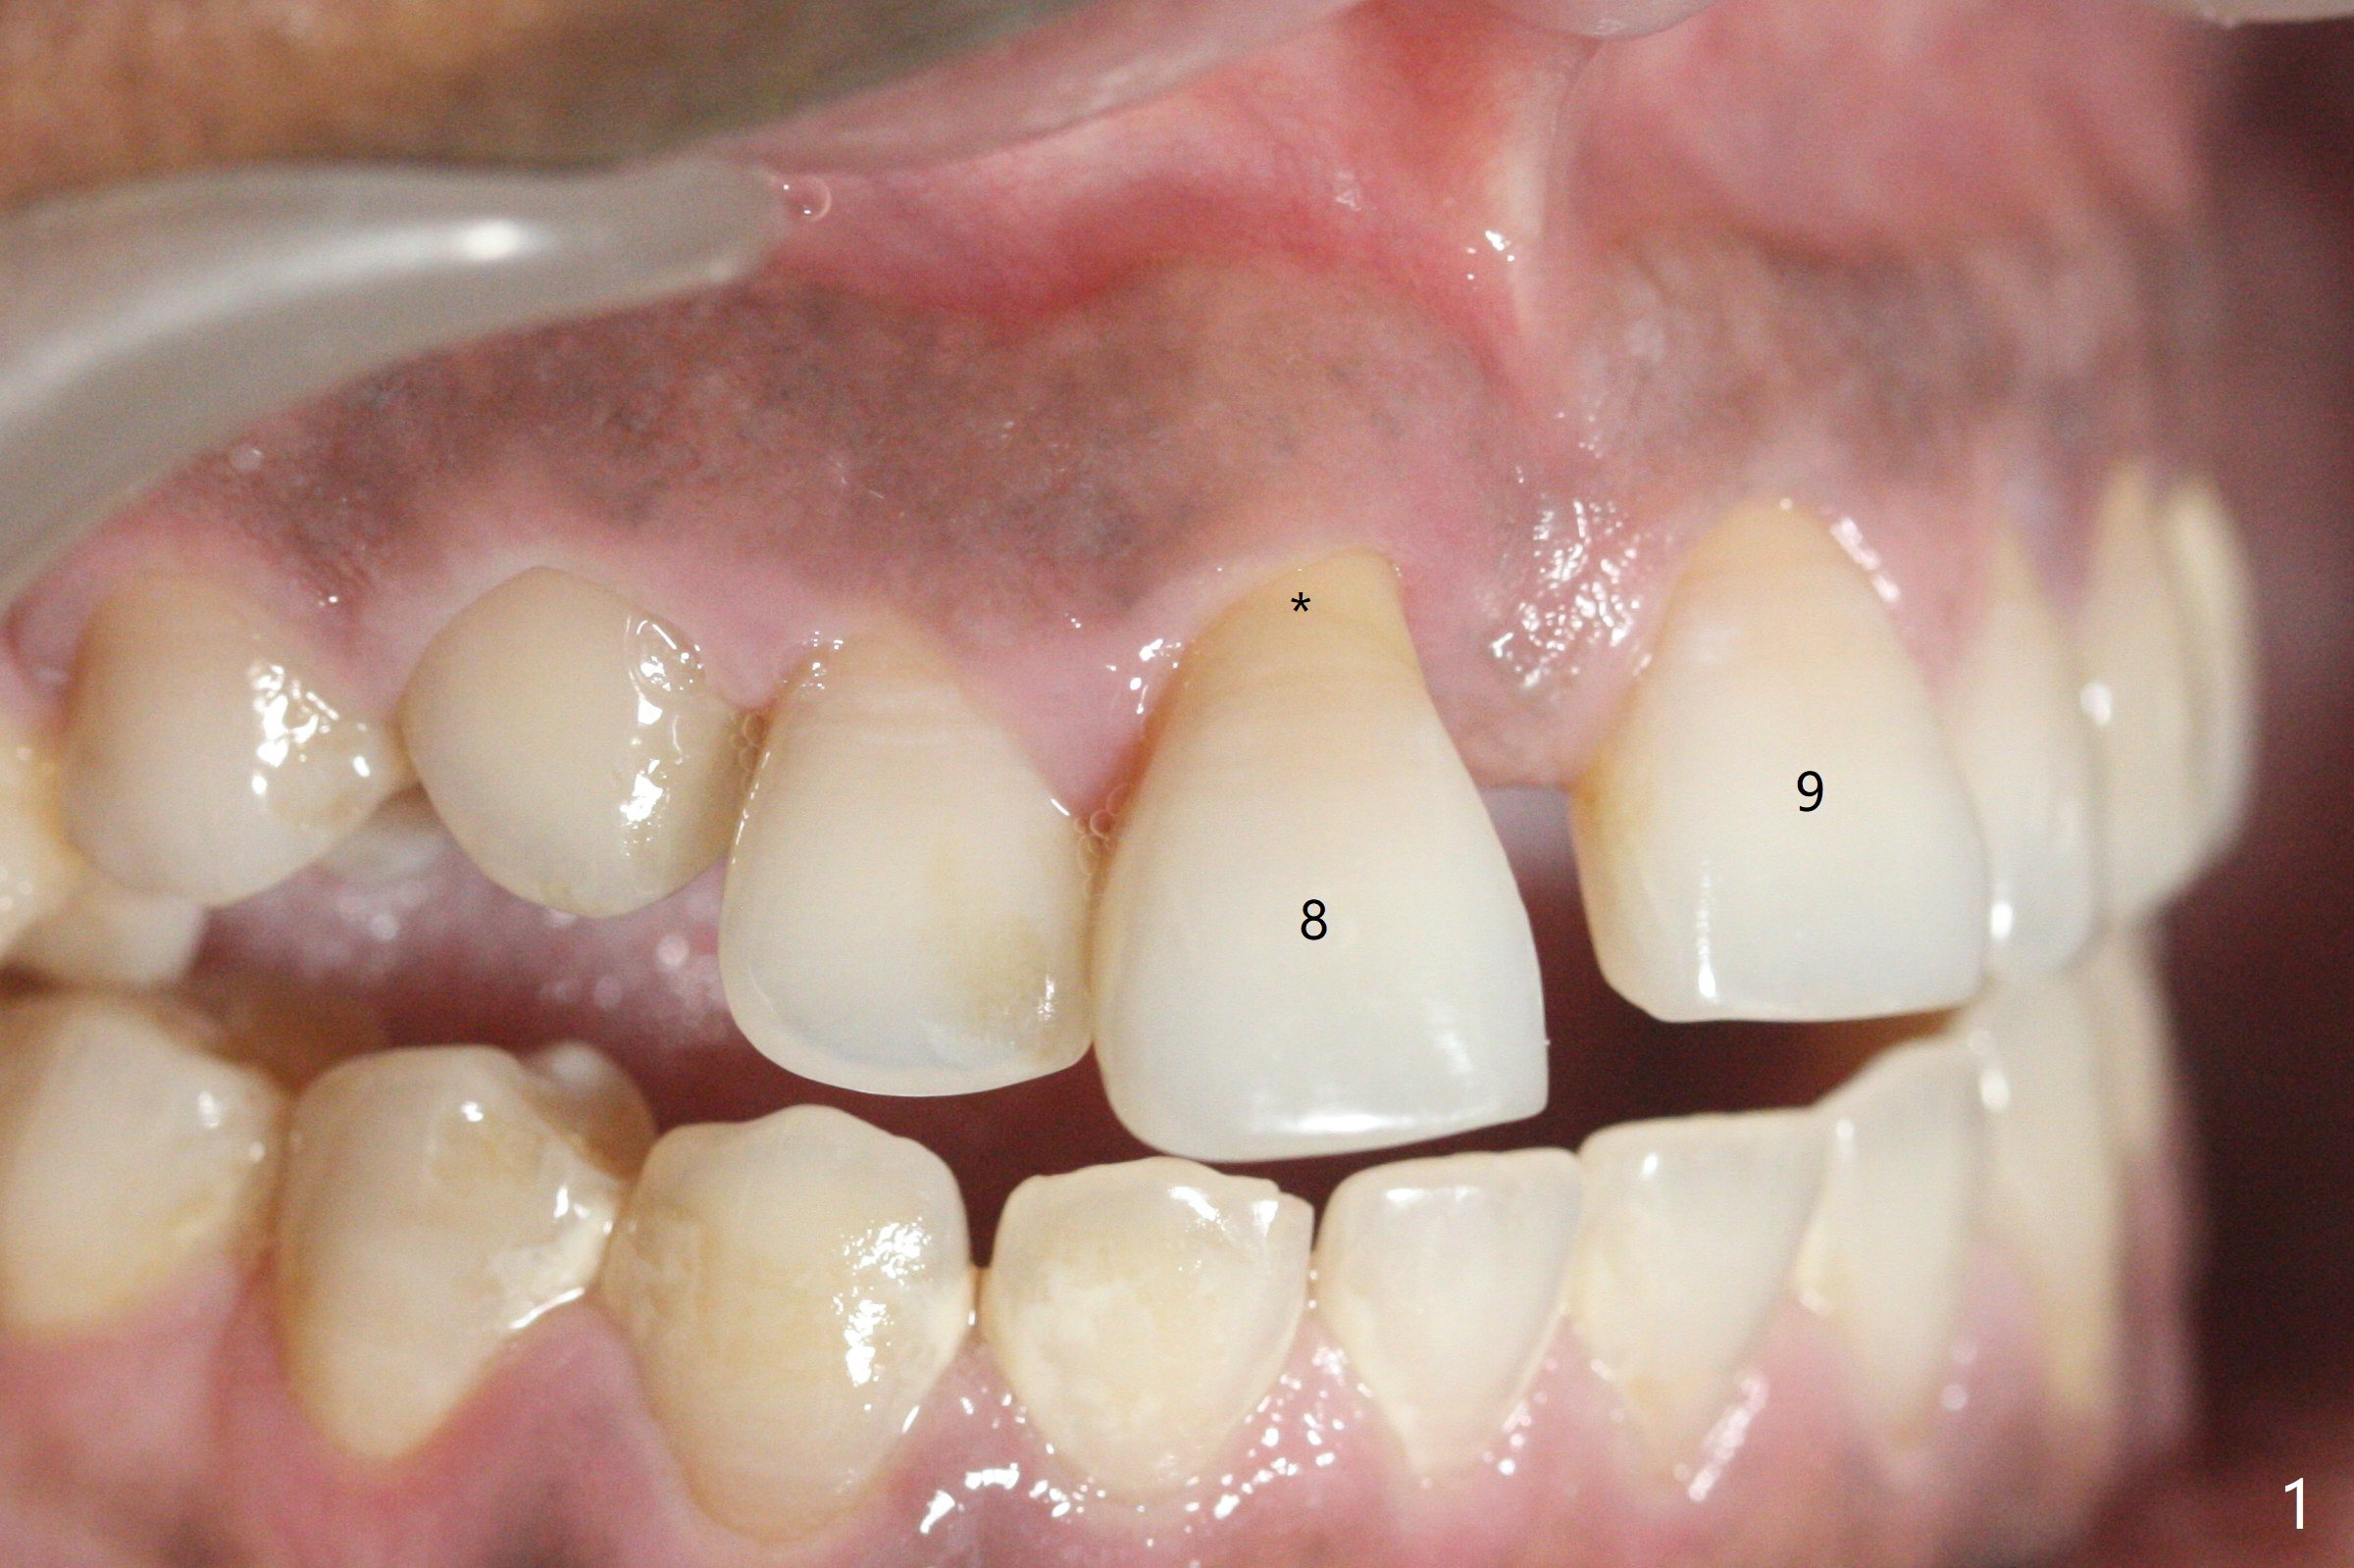

50岁女8号牙远中颊侧冠方移位(图一),牙根暴露(*),前磨牙-前磨牙开合,腭侧牙龈红肿。拔除清创后,使用导板钻洞,徒手植入2.5x13毫米一段式植体,首先将PRF膜插入腭侧,剩余牙槽窝空间植入粘性骨粉(图二:*)。截断拔除牙齿,牙冠掏空,反复调整牙冠长度,使用流动性树脂(flowable composite,图三:*)衬里固定牙冠(C),恰好PRF封闭远中颊侧牙槽窝开口(图四),自然牙冠和一段式植体配合,形成最佳emergency profile,最后牙周敷料进一步封闭牙槽窝(图五),防止骨粉早期脱落,不必担忧敷料不透气。腭侧牙龈红肿(图六)。服用Augmentin两天,患处没有触痛了(图七)。术后九天颊侧牙龈继续延长(图八).